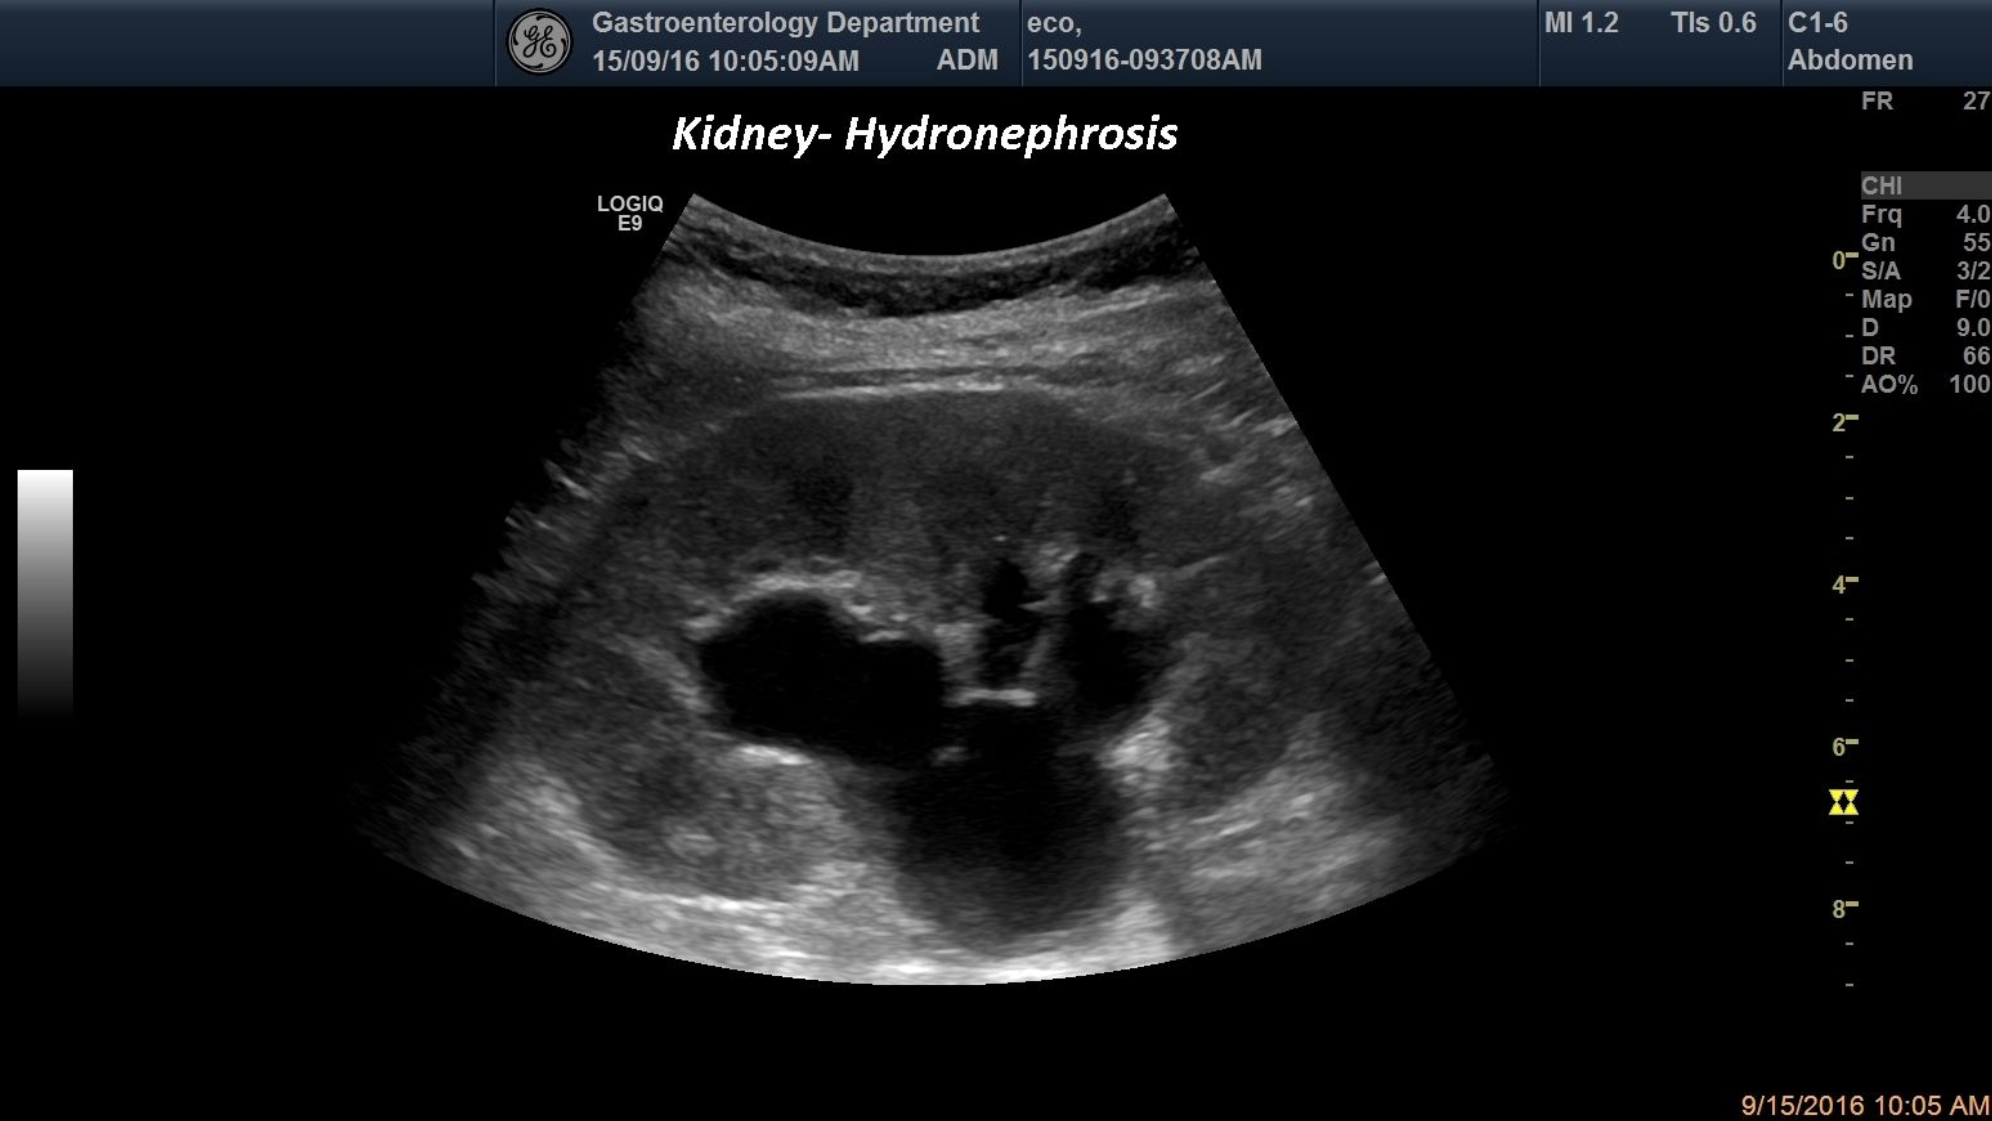

TITLE:   Hydronephrosis

An 34-year-old patient admitted into the emergency room for left lumbar colicative pain, was diagnosed by standard ultrasound with grade II-hydronephrosison her left kidney.

kidney ultrasound, Hydronephrosis